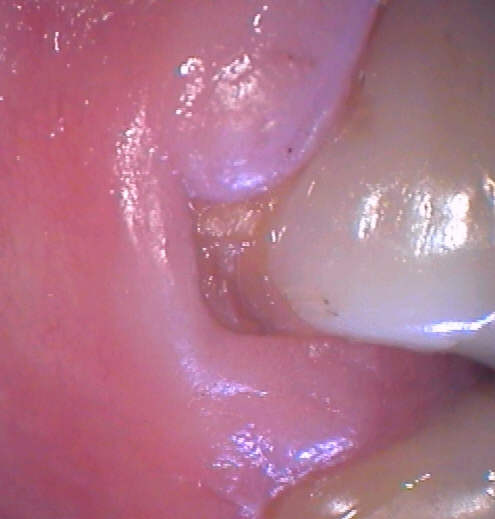

Beginnende Stilmann-Spalte 46 (Klick!).

Sehr schön sieht man die entzündliche, wulstige Ausprägung der Gingiva, die ausbrechenden Zahnhälse an 45 und 46 und die starke buccale Abrasion an 45. Die Krone an 46 ist bei bekannter Anamnese mit Absicht extrem abrasiv gestaltet. Zum Glück hat die Patientin nie den Rat eines Gutachters gesucht.